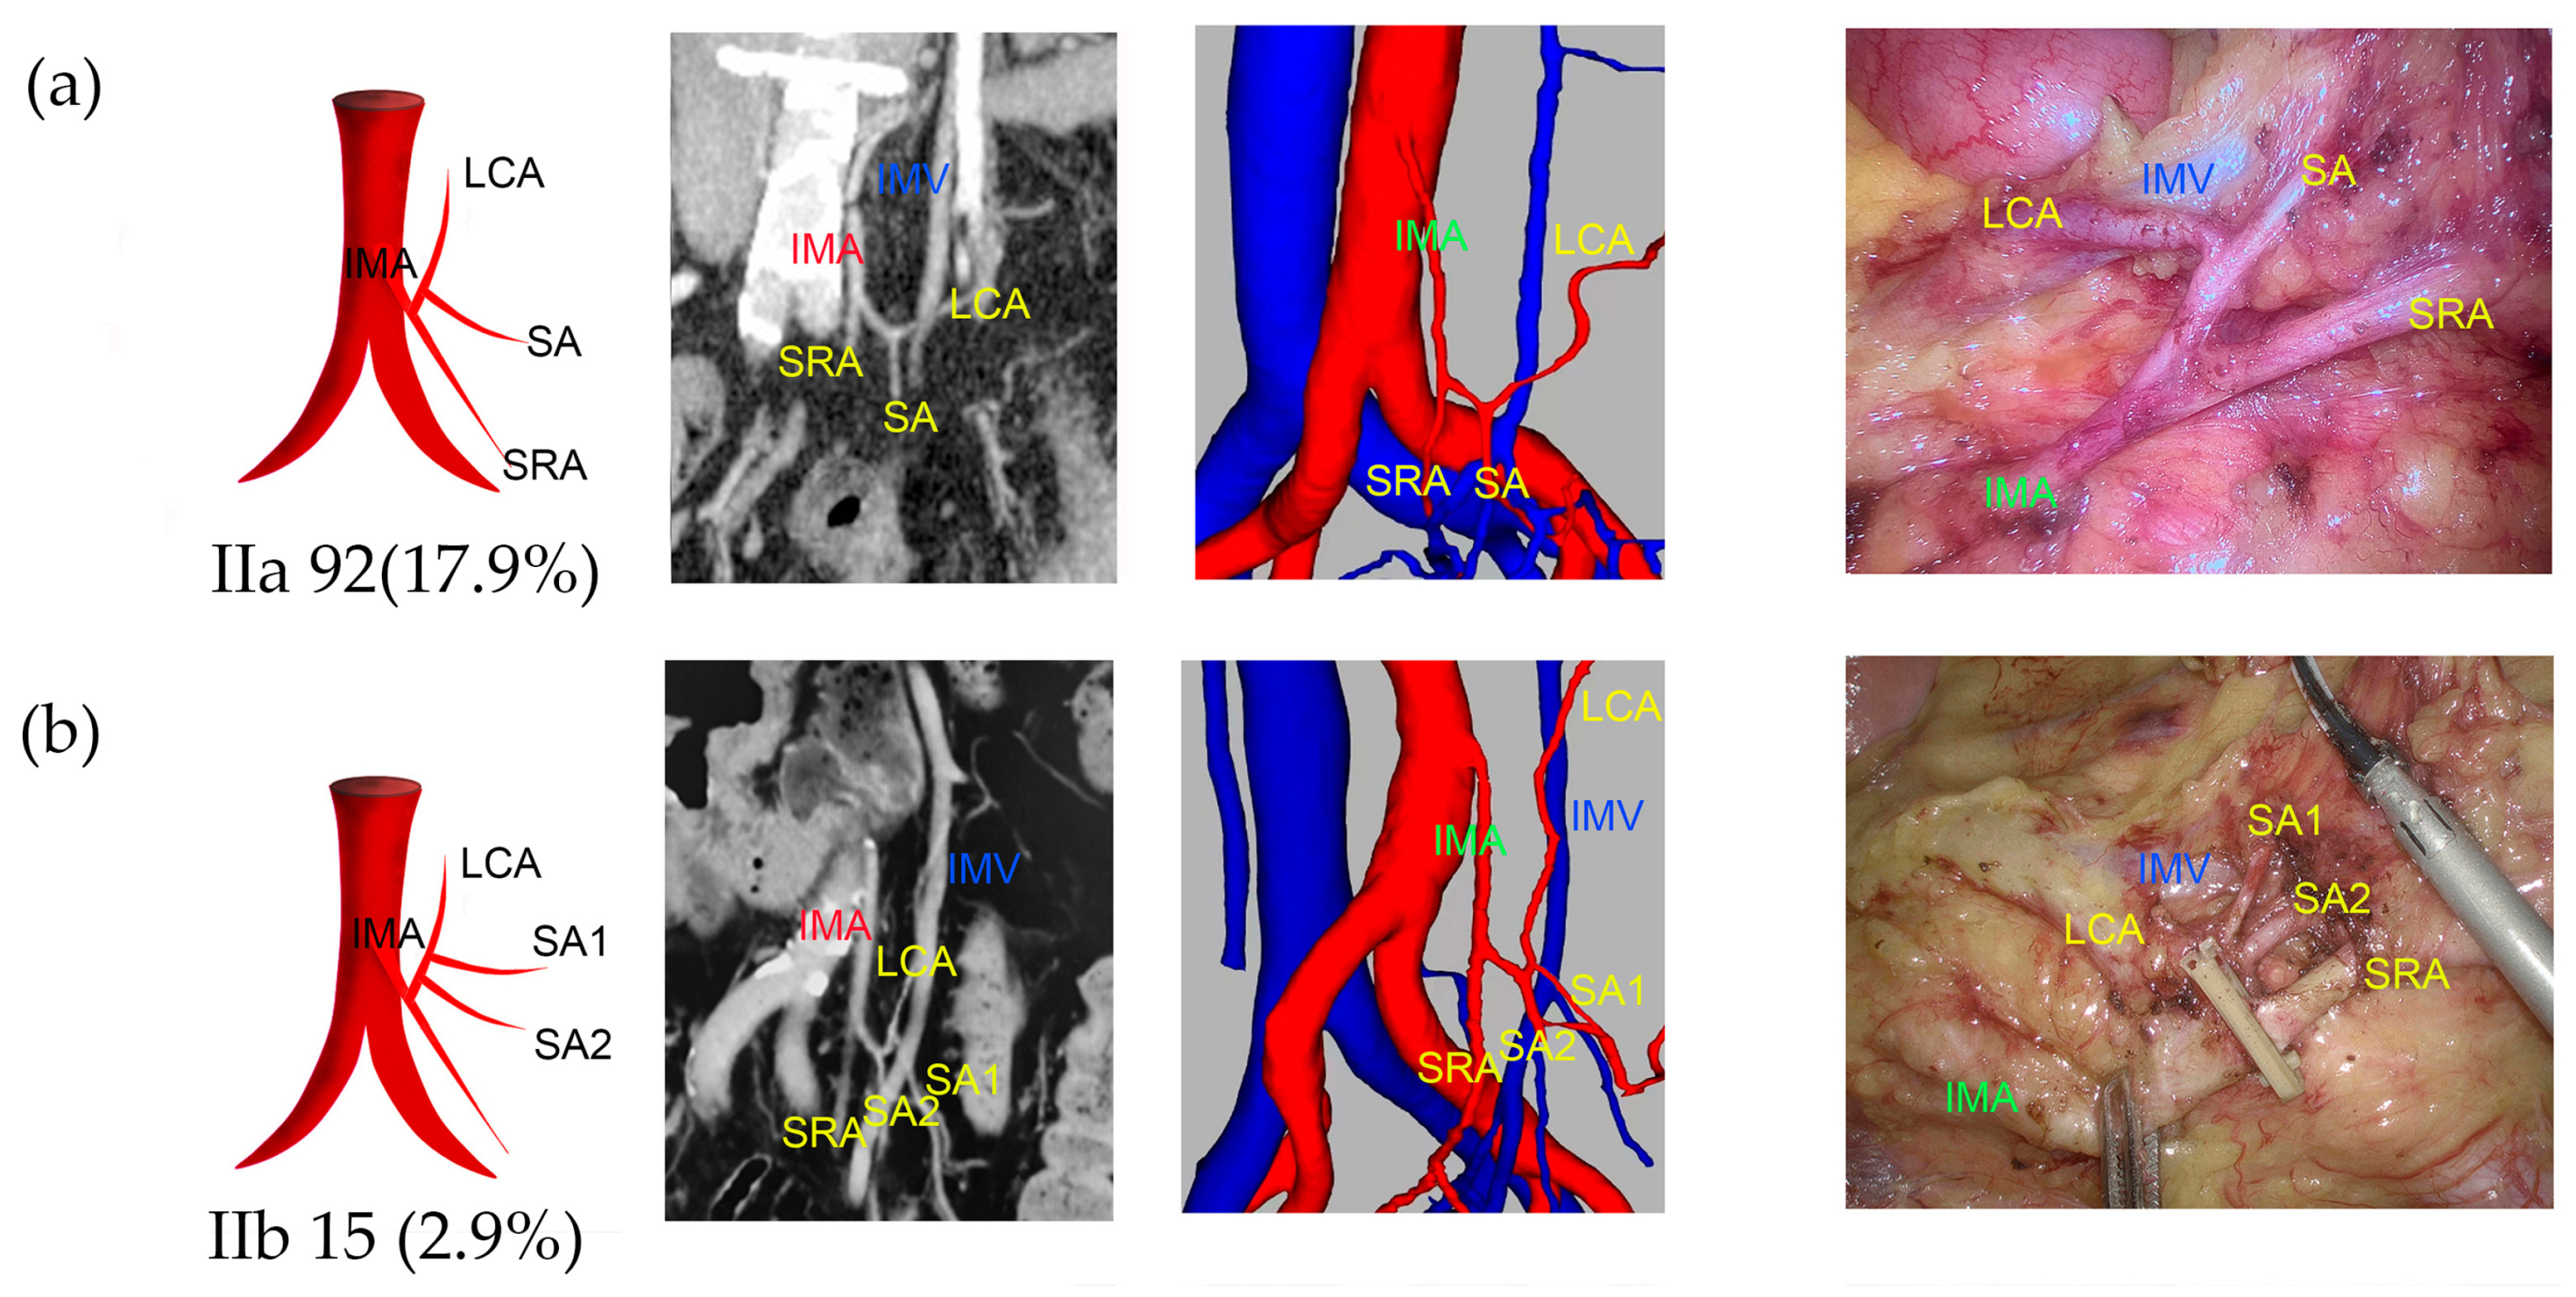

2.4. Types of IMA

3.2. IMA Types